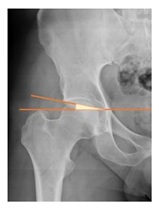

Preoperative and postoperative radiographic data are reported in Table 4. Preoperatively, 18 THR (24.3%) were implanted in skeletally immature children with closed triradiate cartilage (1 ≤ Risser ≤ 3). Radiographic acetabular insufficiency (LCEA < 25° and AI > 13°) was detected in 14 hips (18.9%), while protrusion was present in 3 hips (4.1%) An excessive valgus of the femoral neck was observed in 19 hips (25.7%), while an important varus deformity was present in 7 hips (9.5%).

Postoperative radiographs showed a significant vertical malposition of the cup in 1 case (1.4%), a significant varus stem in 8 cases (10.8%) and a significant valgus stem in 1 case (1.4%). Two patients (2.7%) showed moderate heterotopic bone formation (Brooker ≥ 2), that did not significantly affect the hip motion and symptoms. All those THR that did not undergo revision showed good radiographic osteointegration, with no evidence of implant breakage, radiographic lucencies, bone defects, cup migration, or stem subsidence at the most recent radiographs.